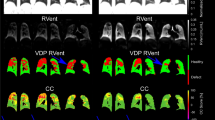

Of the 71 participants, 31 (43.6%) had ultra-low dose CT thorax at baseline, year one and year two (Table 2). There was a significant increase from baseline in the %Bronchiectasis PRAGMA-CF CT score over 2 years (0.82 to 1.24, p = 0.005) but no change in %Disease score (2.78 to 2.25, p = 0.138) (Fig. 2). There was a significant decrease in %Trapped air PRAGMA-CF score (0.13 to 0.07, p = 0.016) over two years but no change in %Mucus plugging (0.57 to 0.33, p = 0.221). Intra-observer and inter-observer reliability were excellent (> 0.8) for the two main PRAGMA CF scores %Disease and %Bronchiectasis (Table E2). There were significant increases in the Bin/A-ratio over two years when examined in the first four generations and across all generations. There were no significant increases over any generations for Bout/A-ratio and BWT/A-ratio (Fig. 3; Table 3).

We did observe improvements in trapped air scores over two years, but despite this saw a progression of bronchiectasis. This may suggest that LUM/IVA has some effect in relieving small airway obstruction caused by inflammation in small airways but is unable to prevent the worsening of bronchiectasis caused by established or persistent infection and associated inflammation. In order to corroborate our findings, we examined BA dimensions throughout the segmental generations and found widening of the airways of our participants. This method has been shown to correlate well with bronchiectasis detected by PRAGMA CF scoring [17]. The increases in BA dimensions in respect to Bin/A-ratio alone over two years, indicates an improvement in mucociliary clearance and thinning of the airway wall as described in a recent study [37]. The BA dimension findings correlate with the PRAGMA CT scores demonstrating that LUM/IVA had some effect on relieving small airway obstruction but the progression of structural lung damage in the form of bronchiectasis continued in our study participants. There is significant variation in the degree of structural lung disease in young children [15] and the clinical response to LUM/IVA in people with CF [38]. CFTR modulators have been shown to improve mucociliary clearance and are likely to improve air trapping [39]. Therefore, LUM/IVA may be effective at improving minor reversible structural lung disease, such as air trapping, but has little effect on more developed and irreversible changes such as bronchiectasis.